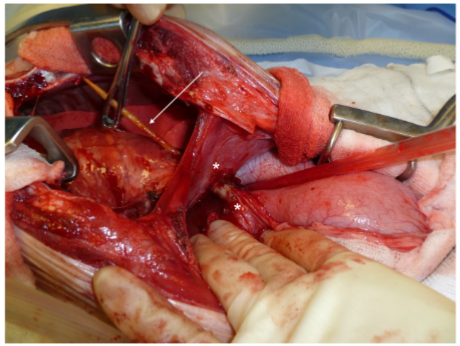

특히 나무가 일종의 빨대가 되어 모세관 현상을 통해 똥물을 복강으로 흘려보내니 복막염 또한 어마어마한게 보통...